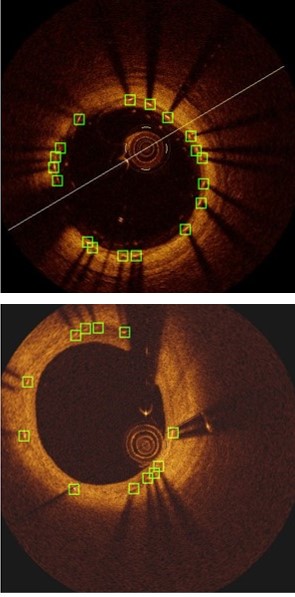

Accurate assessment of neointimal coverage after stent implantation in intravascular optical coherence tomography (IVOCT) images is important to ensure the safety and efficacy of the Percutaneous Coronary Intervention procedure [8]. Unfortunately, manual assessment requires the detection and analysis of thousands of struts within the stent, which is a challenging, tedious and time-consuming task. As shown in Fig. 1, the stent struts are small, and the visual characteristics of the region covering the thick intima (innermost layer of the artery) may make the struts inconspicuous.

Refer to caption

Figure 1: Common vascular features in IVOCT images. The middle image (c) shows the manually labeled stent struts (12 in total), with two green bounding boxes of struts (a) and (b).